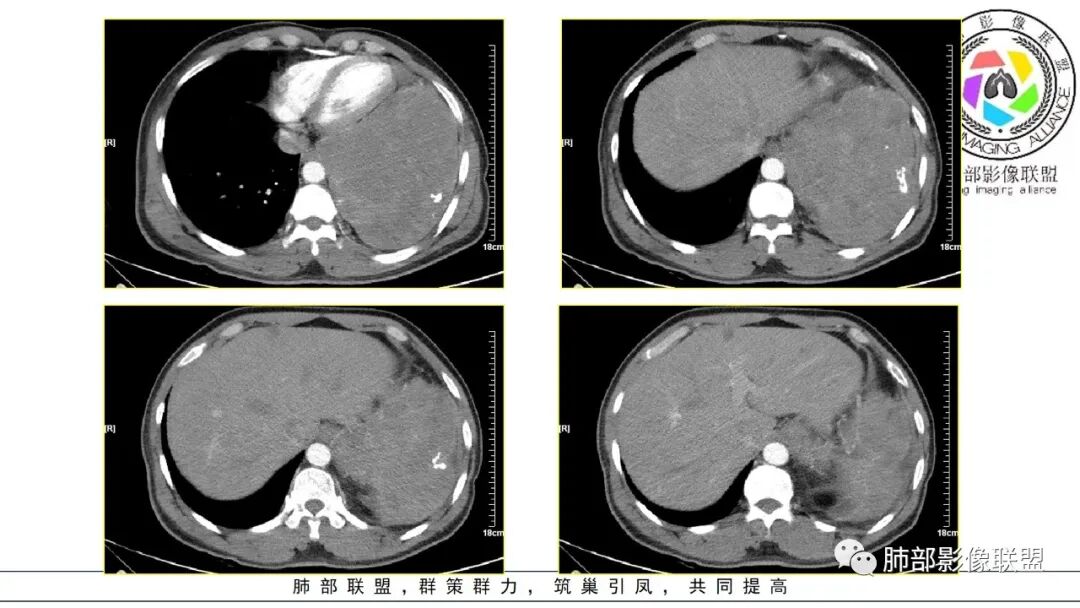

好发于肺胸壁交界区或纵隔交界区,病灶部位对病灶性质判断有较大价值。多单发,有包膜,边界清。

密度:与肿瘤细胞疏松或密集、胶原纤维含量、出血、坏死、囊变及黏液变性等有关。镜下由梭形细胞组成、细胞间由胶原纤维沉积,CT平扫肿瘤实性部分为等、稍低密度,胶原纤维易发生黏液变性或囊变,导致密度不均匀,较少出现钙化。一般肿瘤小,密度多均匀,肿瘤大,多发生坏死、囊变,密度多不均匀。

强化方式:多均匀或不均匀明显强化,增强肿瘤内可见迂曲血管影(蛇纹血管等),肿瘤较大可见“地图样”强化。

恶性倾向:体积较大,多见出血、囊变及坏死;强化多不均匀;呈浸润性生长,与周围组织器官边界不清;出现远处转移等。